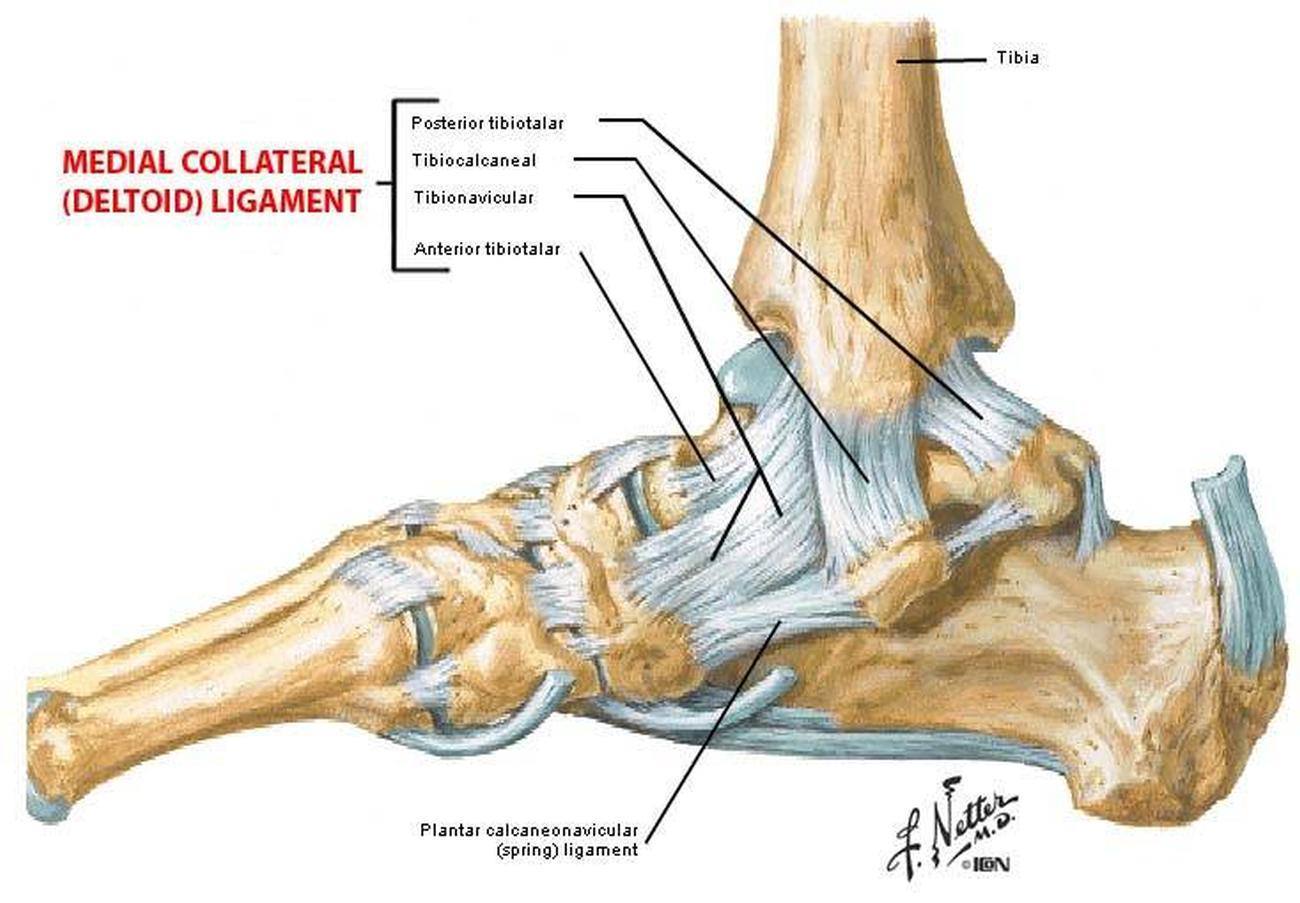

When there is a lateral ankle sprain, which ligaments are affected?

1. Anterior/posterior talofibular ligaments

2. Calcaneofibular ligaments

Distal fibular fracture with rupture of the deltoid ligament

What would cause suspicion of a ruptured deltoid ligament?

Medial bruising and tenderness